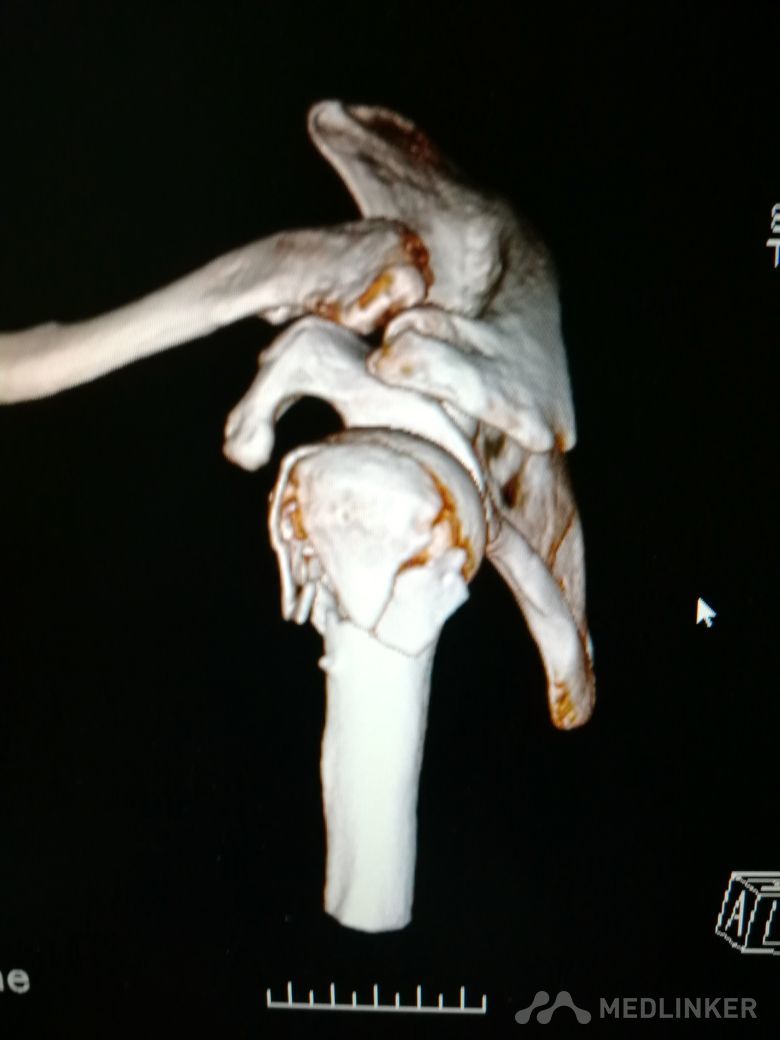

肱骨近端骨折 Neer IV型

患者,女性,55岁,因外伤致左肩疼痛六小时入院,既往无其他慢性病史

查体 右肩肿胀,畸形,活动受限,压痛,皮下淤血,右桡动脉搏动存在

完善相关检查,在腰麻下行右肱骨近端骨折切开复位内固定术

肱骨近端骨折占到肱骨骨折的45%,肱骨近端锁定钢板具有低切迹、高弹性、生物力学性能优良等特点,可以起到角度稳定控制旋转的作用。但是对于严重粉碎性肱骨近端骨折而言,单纯的肱骨近端锁定钢板不一定能够提供稳定的固定,手术之后仍有可能出现内翻塌陷、前后成角、螺钉切出、骨折畸形愈合、骨折不愈合等并发症。